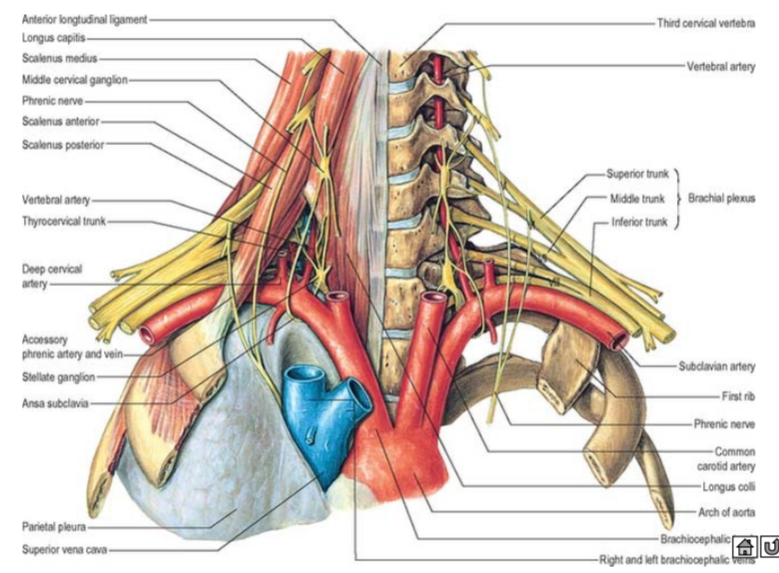

Subclavian a.

Scalene m.

ant.,mid. scalene insertion at rib 1

post. scalene insertion at rib 2

Thyrocervical trunk

subclavian vein 在ant. scalene m. 上方

Neck

Triangle